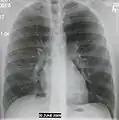

The discovery of x-rays made it possible to determine the anatomic type of pneumonia without direct examination of the lungs at autopsy and led to the development of a radiological classification. Early investigators distinguished between typical lobar pneumonia and atypical (e.g. Chlamydophila) or viral pneumonia using the location, distribution, and appearance of the opacities they saw on chest x-rays. Certain x-ray findings can be used to help predict the course of illness, although it is not possible to clearly determine the microbiologic cause of a pneumonia with x-rays alone.